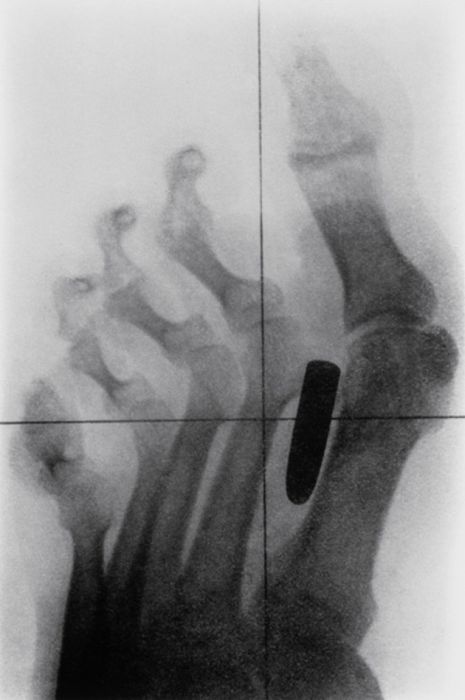

Рентгеновские снимки людей, которые умудрились сами или с чужой помощью разместить внутри своего организма разные посторонние предметы. От вилок и ножей до пуль и бензопилы (!!!). По этическим соображениям обычные снимки таких травм и повреждений выкладывать нельзя, зато рентгеновские можно – на них травмы видны достаточно условно, хоть и очень понятно.